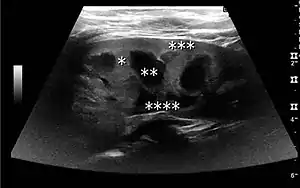

The hydronephrosis is typically graded visually and can be divided into five categories going from a slight expansion of the renal pelvis to end-stage hydronephrosis with cortical thinning (Figure 15). The evaluation of hydronephrosis can also include measures of calyces at the level of the neck in the longitudinal scan plane, of the dilated renal pelvis in the transverse scan plane and the cortical thickness, as explained previously (Figure 16 and Figure 17).[1]

Figure 16. Hydronephrosis with dilated anechoic pelvis and calyces, along with cortical atrophy. The width of a calyx is measured on the US image in the longitudinal scan plane, and illustrated by ‘+’ and a dashed line.[1]

Figure 17. Same patient as in Figure 16 with measurement of the pelvis dilation in the transverse scan plane illustrated on the US image with ‘+’ and a dashed line.[1]